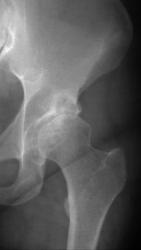

Добрый вечер, коллеги! Направлена женщина 1977 года рождения на рентгенографию т/б суставов с диагнозом: ДОА? Жалобы на непостоянные боли в течение последнего года. Снимок не резкий, извиняюсь. Написал кисту крыши вертлужной впадины и ДОА II-й степени. Прав?

ТБС неубедительно. В первую очередь я бы подумал об асептическом некрозе головки бедренной кости.

Головка слегка уплощена если сравнивать с правой.

Отвечаю по порядку: 1. О туберкулёзе мыслей не было (нет остеопороза, секвестров, местно нет атрофии мышц, норма, со слов пациентки, по ФЛГ); 2. Если не на кисту, то на что это похоже? Думал на эозинофильную гранулёму, но что-то не прочувствовал; 3.Травмы не было, отрицает; 4. Асептический некроз не рассматривал, так как процесс выражен во впадине. Потом уже, когда пациентка ушла со снимком и моим описанием, пришла запоздалая идея, что надо было доснять с ротацией бедра, "вывести" головку...

Асептический некроз крыши вертлужной впадины и головки бедра

на фоне её кистовидной перестройки (странно, что участники отвергли)!

Отлично, Медея! Сумела улучшить денатурированную репродукцию снимка, а до того увидеть суть проблемы. Вот что значит объёмное восприятие объекта, свойственное Настоящему Рентгенологу. Да, здесь множественные разнокалиберные кисты почти по всему периметру впадины, а в обл. крыши одна близка к прорыву в полость сустава. В этом случае томография для уточнения стадии необходима.

А вот Makcimalist не смог выбраться из плоскости снимка. Головка бедра только кажется изменённой. Из-за наслоения патологии впадины.

Кистовидная перестройка вертлужной впадина имеется, безусловно. Первичная или вторичная? Но имеется кистовидное просветление, которое относится к головке, а не к впадине. И сколько не абстрагируйся от суперпозиции головки и впадины, без второй проекции структуру головки не выяснить.